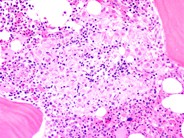

Bone marrow granuloma - 2.

Category: Reactive Marrow

The granulomatous lesion is shown at higher magnification to illustrate the cellular composition of macrophages with eosinophilic cytoplasm and scattered lymphocytes and plasma cells.